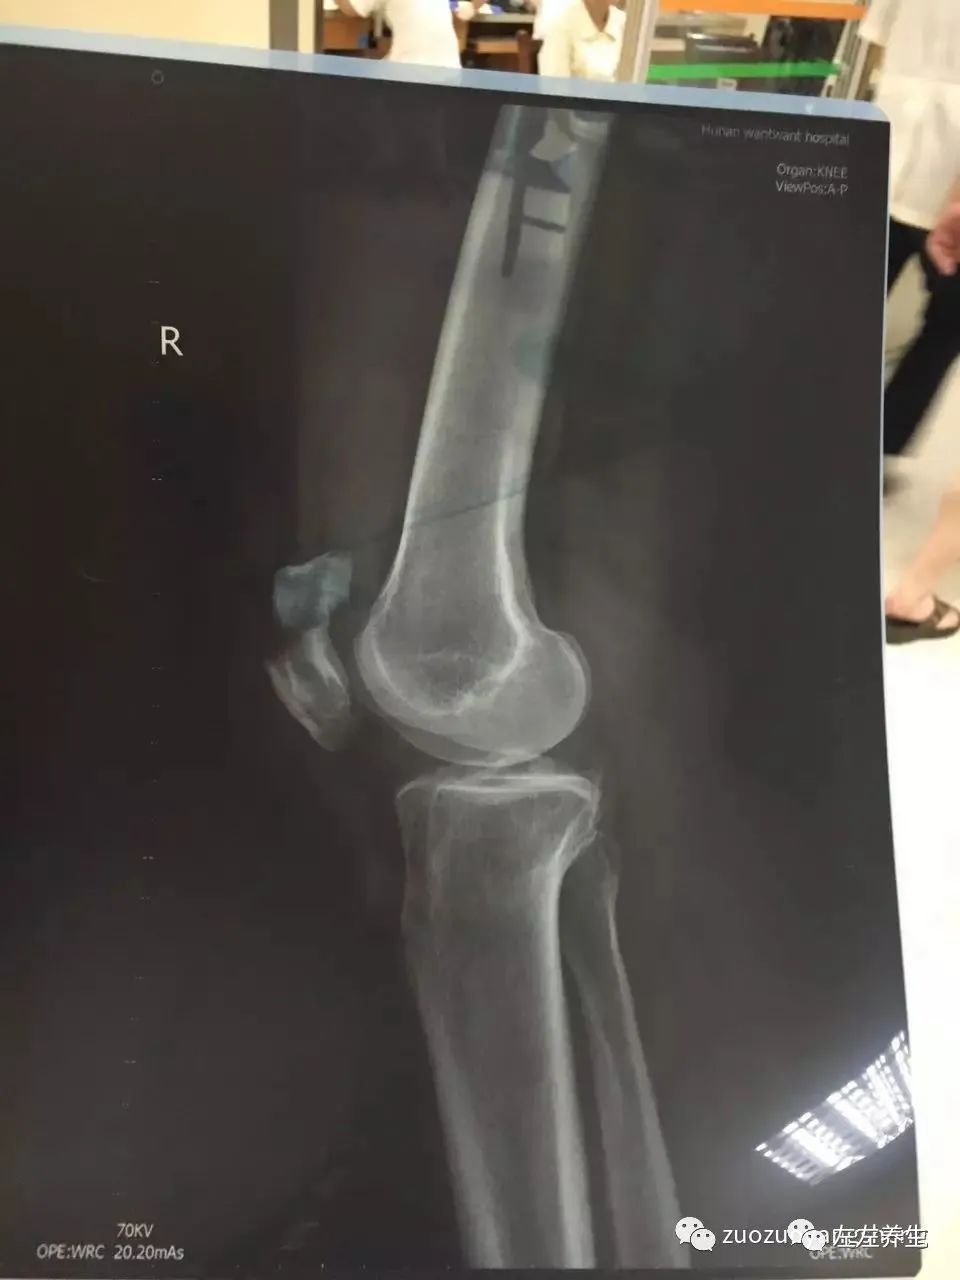

2016年8月21日一早,自己都还没完全醒来,就被楼下好心的邻居敲门弄醒。原来是母亲在楼下摔了一跤,膝盖受损。后带母亲到医院做CT后,被诊断为膝盖髌骨粉碎性骨折。

面对妈妈骨折这个的问题,非常清楚,原始点是没有办法的(如果是骨裂,则可以包裹温敷),只能寻求医院的救助。最后经过家人商量,于8月21日下午入住浏阳社港骨科医院。跟医生讨论治疗方案后,决定手术打钢钉固定髌骨的治疗方案。(当时特别想让医生使用传统手法固定,可以免受手术切割、麻药、输液等伤害,医生则不建议,因为受伤是在腿上,需要躺床上三个月不动,不能下地。这样完全不能动,可能带来身心的全面伤害。最后只能放弃传统手法固定方案。其他原始点家人如果遇到骨折之类,需综合判断,如允许,建议尽量规避手术方案。)之前非常担心手术前后过多的输液,会太过寒凉,怕母亲的身体无法承受。不过还好,浏阳的这个骨科医院多采用传统治疗方法,输液并不多。其次,我带了姜粉、红参、热水袋,电热毯等内外热源,让她每天坚持使用,及时补充内外热源。